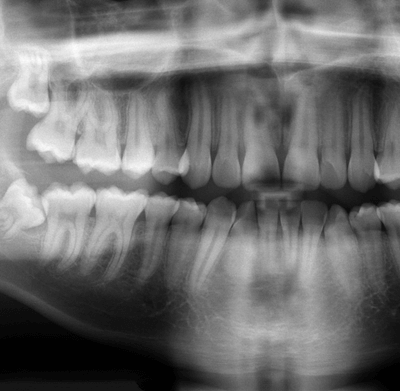

É um exame de raios-x, específico, também chamado de RX panorâmico. É, essencial em medicina dentária, pois possibilita recolher informações do segmento inferior da face, particularmente com visualização das arcadas dentárias. Através dele fica a conhecer-se toda a estrutura óssea e dentária.

É utilizado, principalmente, para estudo de diversas patologias dos dentes, sua disposição, número e estudo de próteses.

Este exame é feito utilizando-se um aparelho denominado ortopantomógrafo, no qual o técnico de radiologia coloca a boca do paciente de forma apropriada e imóvel, enquanto o aparelho se move ao seu redor, emitindo raios-X em diversos ângulos.